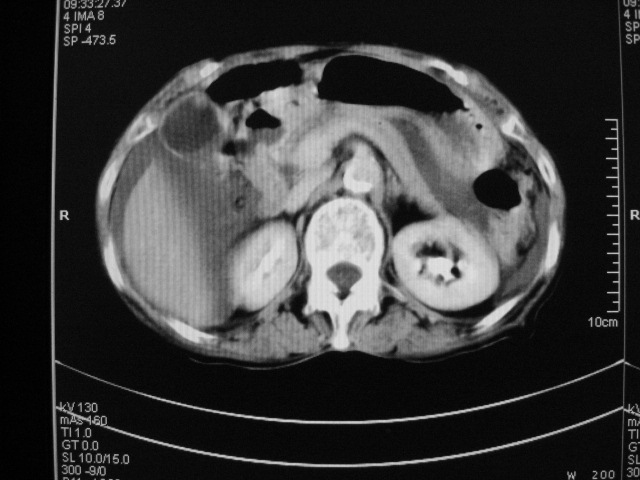

以下是引用快乐男生在2007-9-20 15:32:00的发言:[br]图像质量不好:[br]胆囊增大,囊壁增厚,[br]可见结节突出囊腔内,[br]增强后与囊壁相仿.[br]考虑多为胆囊慢性炎症伴有胆囊体部的息肉